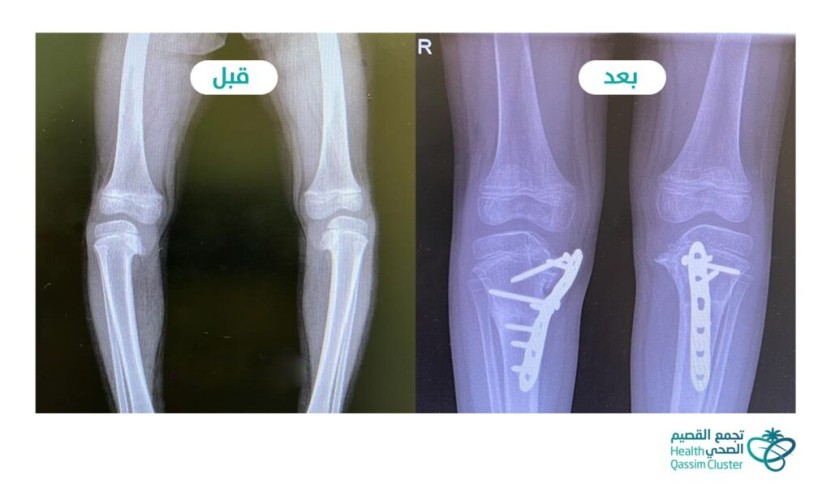

تمكن فريق طبي متخصص في جراحة العظام بمستشفى الولادة والأطفال ببريدة من علاج تقوس الساقين لطفلة في السنة الخامسة من عمرها، بعد إجراء تدخل جراحي استغرق أربع ساعات، وتكلل بعد توفيق الله بالنجاح.

وقال تجمع القصيم الصحي: أن الطفلة راجعة برفقة ذويها عيادة جراحة العظام للأطفال في المستشفى وهي تعاني من اضطراب بالمشي وتشوه شديد بالساقين على شكل تقوس كبير؛ مما سبب لها صعوبة في حركة المشي لديها.

وأضاف: بعد إجراء التقييم السريري والفحوصات الإشعاعية والمخبرية اللازمة بينت إصابتها بمرض “داء بلاونت” ، وهي حالة مرضية يكون فيها عيب خلقي في غضاريف النمو لأعلى الساقين يؤدي إلى تقوس الساقين، وتزداد شدته مع نمو الشخص المصاب وتقدمه في العمر.

وعلى ضوء نتائج الكشف السريري والفحوصات الاشعاعية قرر الفريق المعالج إجراء عمل جراحي تمثل في إجراء قص عظمي تصحيحي مزدوج في كل ساق، وتثبيت العظام بشريحة معدنية ومسامير خاصة، حيث تم إجراء العمل الجراحي للساق اليمنى واليسرى في جلسة واحدة استغرقت أربع ساعات.

وبعد إجراء العملية الجراحية ومتابعة الطفلة من قبل الفريق الطبي والتمريضي وتحسن حالتها تمكنت من المغادرة إلى المنزل، واعطائها موعدًا للمتابعة في عيادة العظام، وبعد المتابعة تبيّن الالتحام التام لمكان القص العظمي واستقامة الساقين، واستطاعت الطفلة -ولله الحمد- المشي بشكل سليم دون عرج أو ميلان.